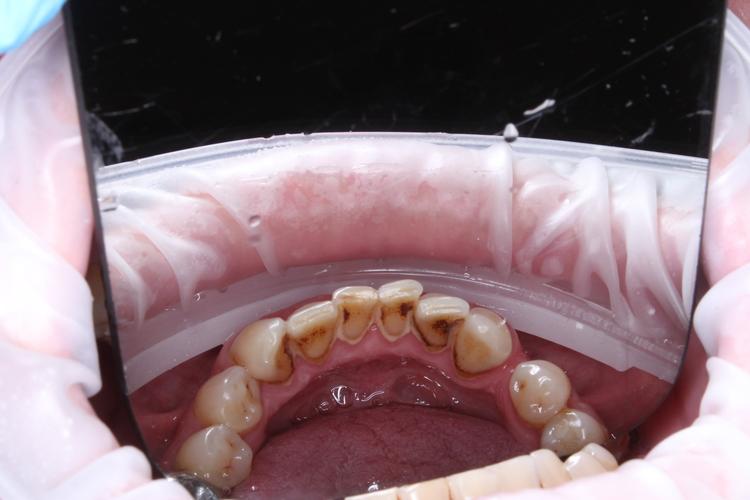

Профессиональная гигиена верхней фронтальной группы зубов

Во время процедуры удален пигментированный зубной налет и камень, проведена полировка зубов. После снятия зубных отложений можно оценить состояние зубов: видна старая пломба и кариозная полость.